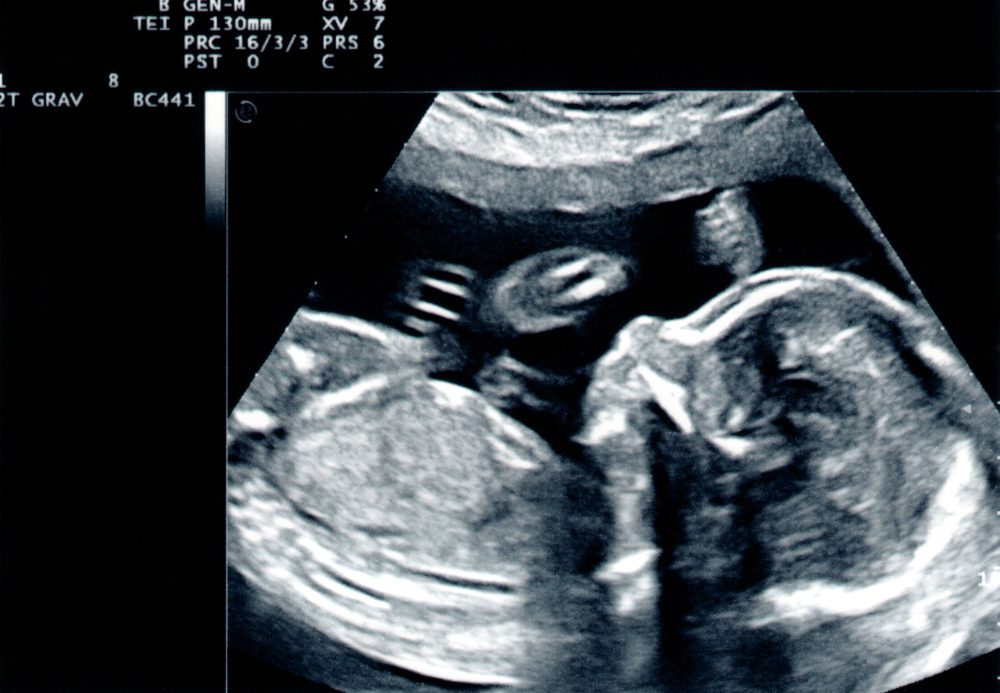

Teherré vált áldott állapot

A kép csak illusztráció